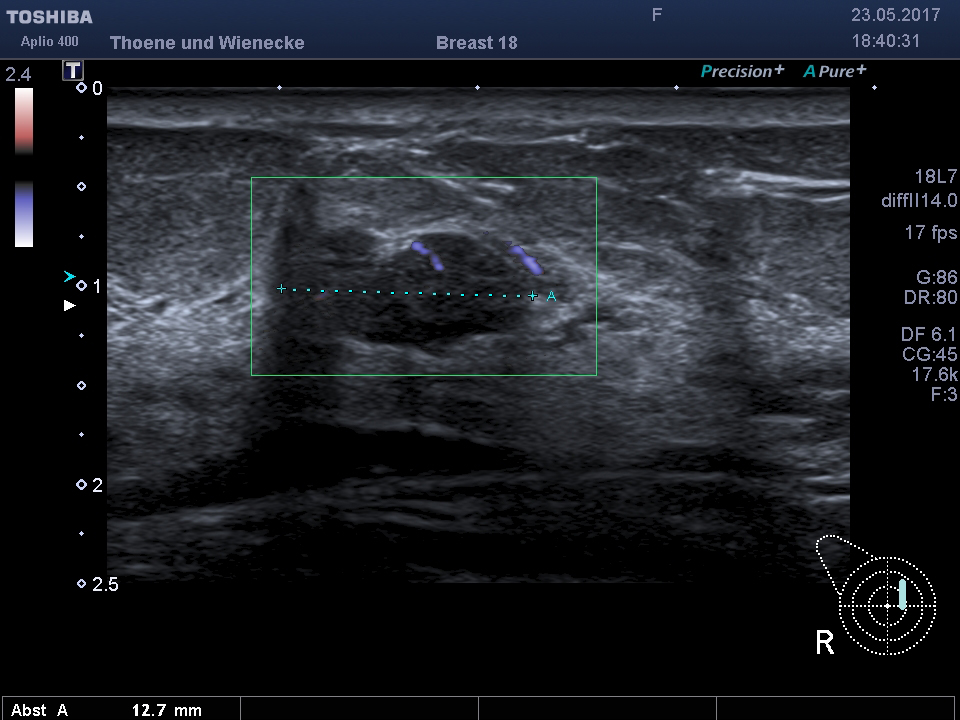

Der Ultraschall ist eine Untersuchung ohne Strahlenbelastung. In unsrer Praxis werden hochauflösende Ultraschallköpfe verwendet, die eine hohe Genauigkeit und sehr gute Auflösung ermöglichen. D.h. auch kleinste Veranderungen können schon gesehen werden. Mit der 3 D Sonographie können Veränderungen des Gewebes in ihrer Abgrenzung zum normalen umgebenden Gewebe besser beurteilt werden als nur mit der 2 D Methode. Bösartige Knoten bilden Ausläufer in das umgebende Gewebe, die wie kleine Strahlen einwachsen. Diese Phämomene können mit der 3 D Sonographie beurteilt werden, die Unterscheidung zwischen gutartigen und bösartigen Veränderungen wird genauer und die Rate an unnötigen Biopsien kann vermindert werden.